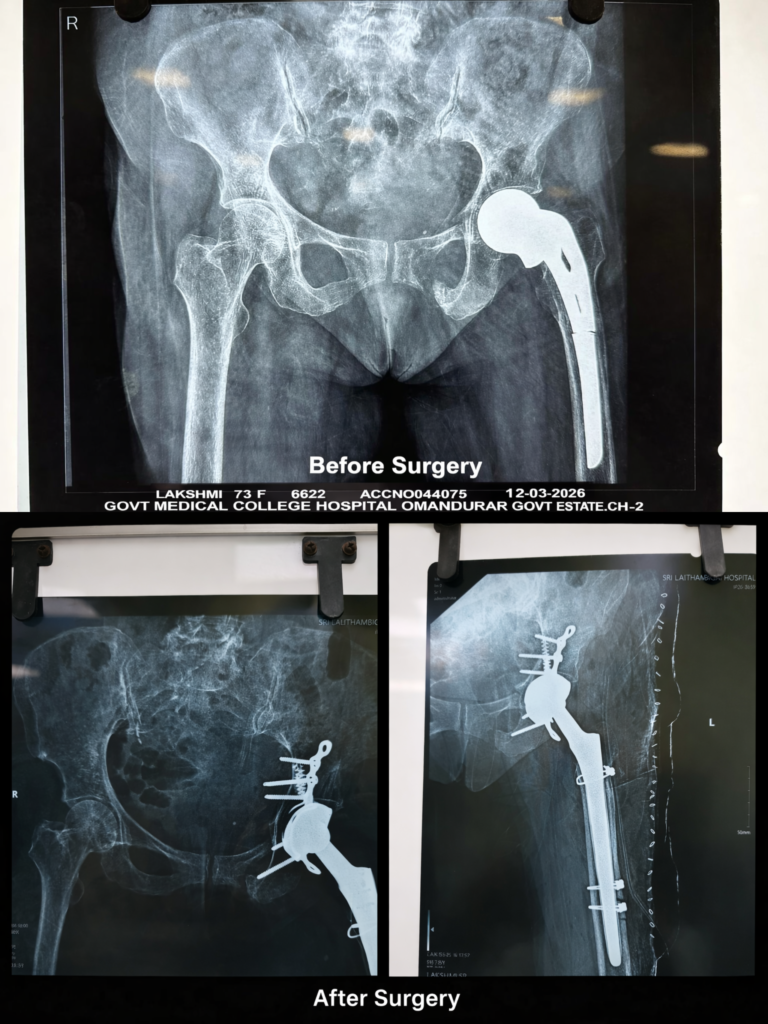

Hip Replacement

A revision total hip arthroplasty was performed via the lateral Hardinge approach. Both the proximal and distal components of the femoral stem were difficult to extract. A cortical window was therefore created distal to the stem to facilitate removal of the broken prosthesis from below. Subsequently, the posterior column was stabilized with plating. Long iliac screws were used, achieving secure fixation in both the ilium and ischium. A dual mobility acetabular component (44 mm) with a 32 mm femoral head was implanted. A long uncemented femoral stem (15 × 225 mm) was utilized to bypass the cortical window. Stabilization was augmented using cerclage cables: one placed over the cortical window following replacement of the femoral cortex, one at the calcar, and one distally. A stable hip construct was achieved intraoperatively, with no limb length discrepancy noted. Full weight-bearing mobilization is planned after 48 hours. The pubic fracture was managed conservatively, as satisfactory fixation and stability were achieved through the ilium and ischium.